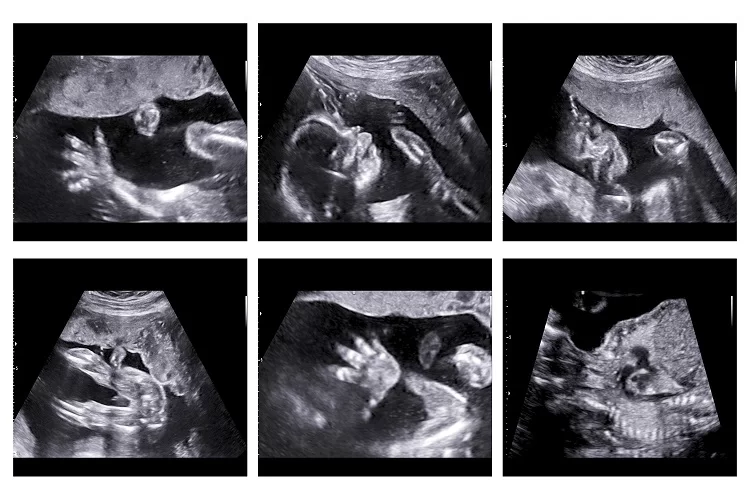

בפוסט שפרסמה ברשתות החברתיות, כתבה י': "לפני כמה חודשים יצאתי מרופאה שלא הכרתי עם הפניה להפלה ודמעות בעיניים. הגעתי אליה בעיצומו של הסגר הראשון, אחרי שבשבוע השישי להיריון היה לי דימום רציני, היא עשתה אולטרה-סאונד וראתה עובר קטן בלי דופק. ליתר ביטחון קבענו תור לשבוע אחר כך. הגעתי שוב, היא עשתה אולטרה-סאונד חוזר, קבעה שאין שינוי ושלחה בדחיפות להפלה עוד באותו יום.

"דווקא המשפט הזה זעזע בי משהו. נסעתי הביתה והחלטתי לחכות. על דעת עצמי קבעתי תור לטכנאית אולטרה-סאונד, שגם אותה לא הכרתי והגעתי בחשש לבדיקה. אתם יכולים לנחש מה היא ראתה שם, עובר חי מאוד בשבוע השמיני, עם דופק".